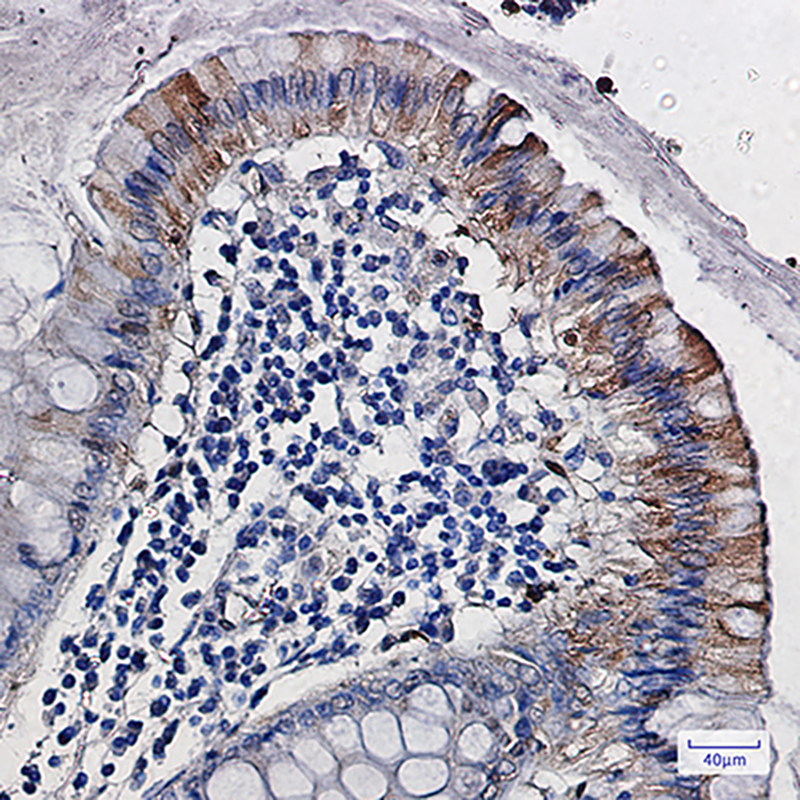

IHC 1/50-1/100 Human,Mouse,Rat